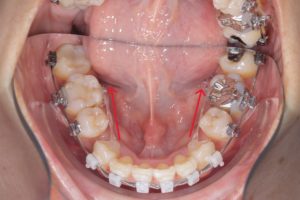

他にも

前突を伴わない重度叢生の症例でも

抜歯してスペースを確保することがあります。

治療前

第一小臼歯抜歯後1カ月経過。

中切歯と犬歯の間にオープンコイルを入れ

側切歯のスペース作り開始。

抜歯後5カ月経過。側切歯にブラケット装着。

抜歯後10カ月経過。舌側にリンガルボタンを装着。

パワーチェーンを使ってスペース閉鎖中。

前歯にスペースが開かないように、犬歯~犬歯を連続結紮。

このような重度叢生の場合も抜歯して作った

スペースを利用しレベリングをするケースもあります。